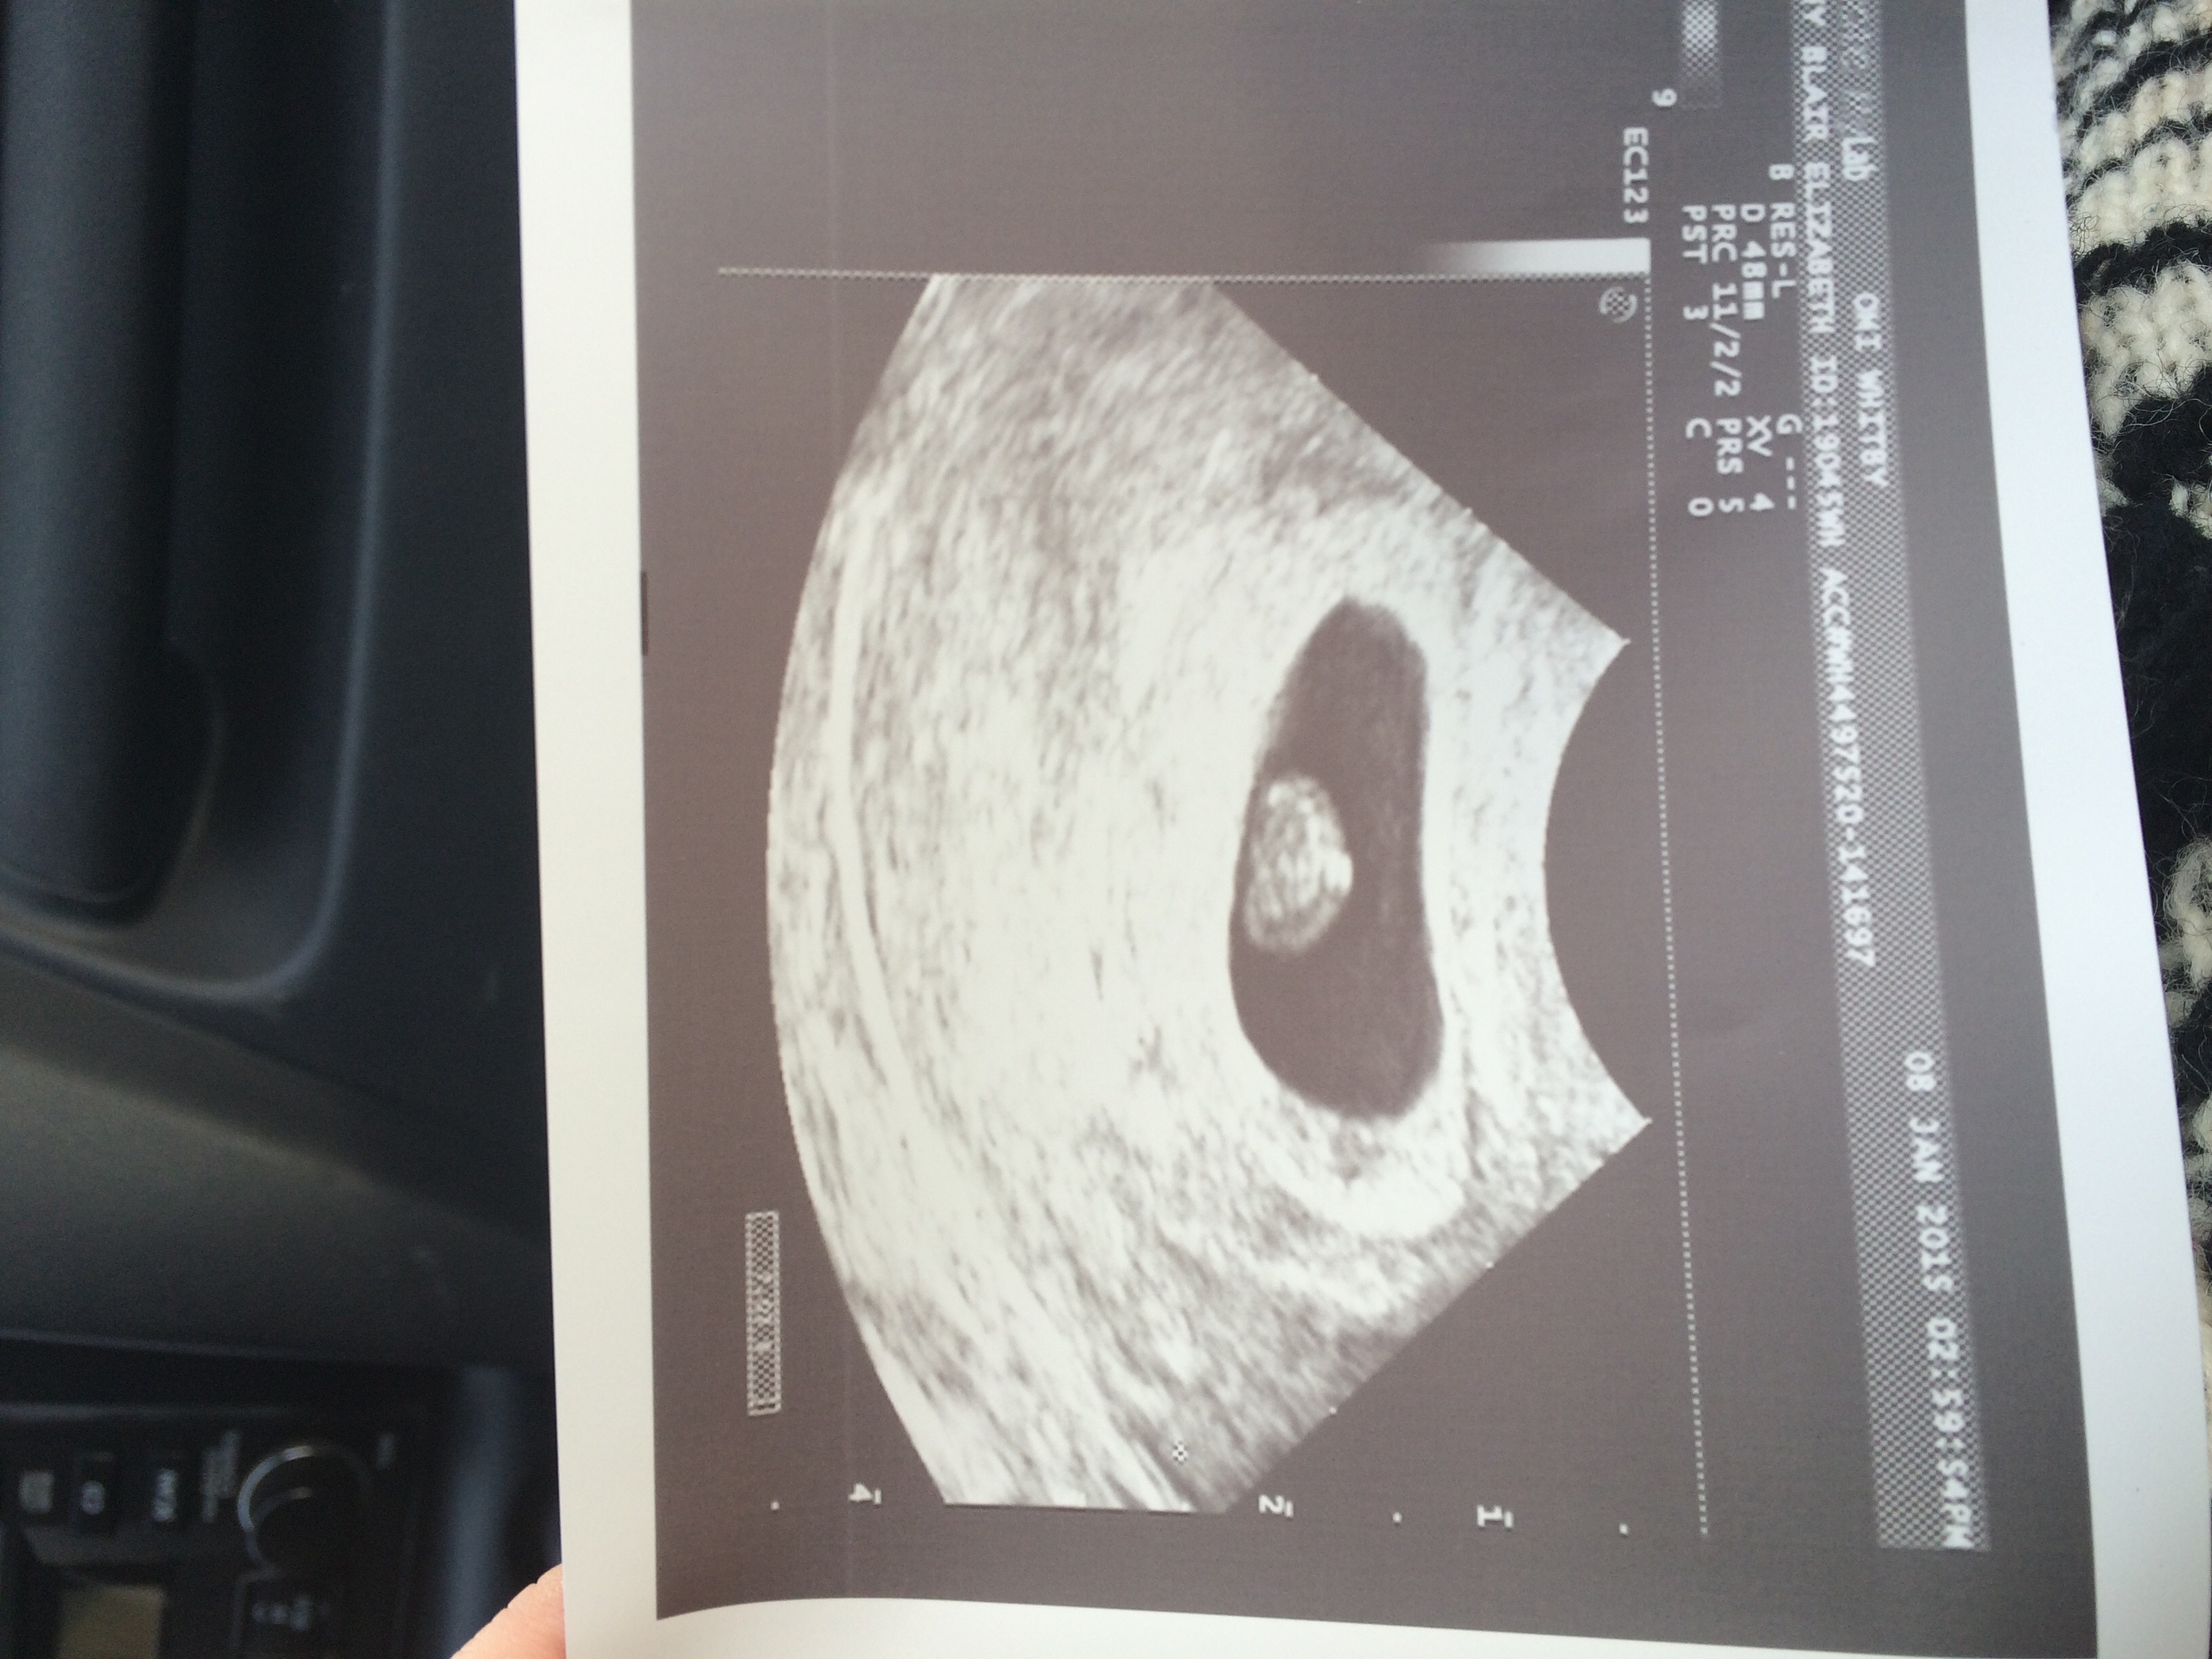

I just got back from my ultrasound and everything looks good so far! I saw the baby's heartbeat but I can't help but be constantly worried. I wish there was a "jump to 12 weeks" option. My previous loss was at 8 weeks so this is a big mental hurdle for me. Poor little dot of mine has been through 3 ultrasounds so far. Hope this is the last for a few weeks to give the little one a rest from being poked and prodded.

Perfect little heartbeat of 156 seen 1/7/15

EDD 8/21/2015 Team Green!